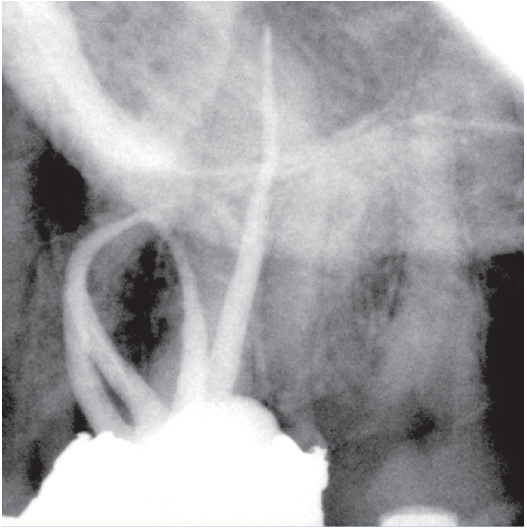

Before

After

Before Root Canal treatment

After Root Canal treatment